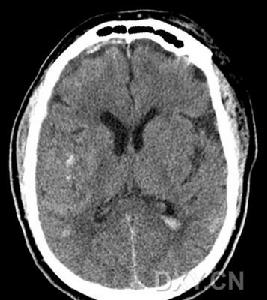

4、顱腦CT可見腦內大小不等、邊界不清的低密度灶。

5、放射學檢查:常規頭顱放射學檢查對散發性腦炎的診斷無重要價值。頭顱CT有時可見大腦半球多個散在的軟化灶,對排除占位性病變有一定意義。